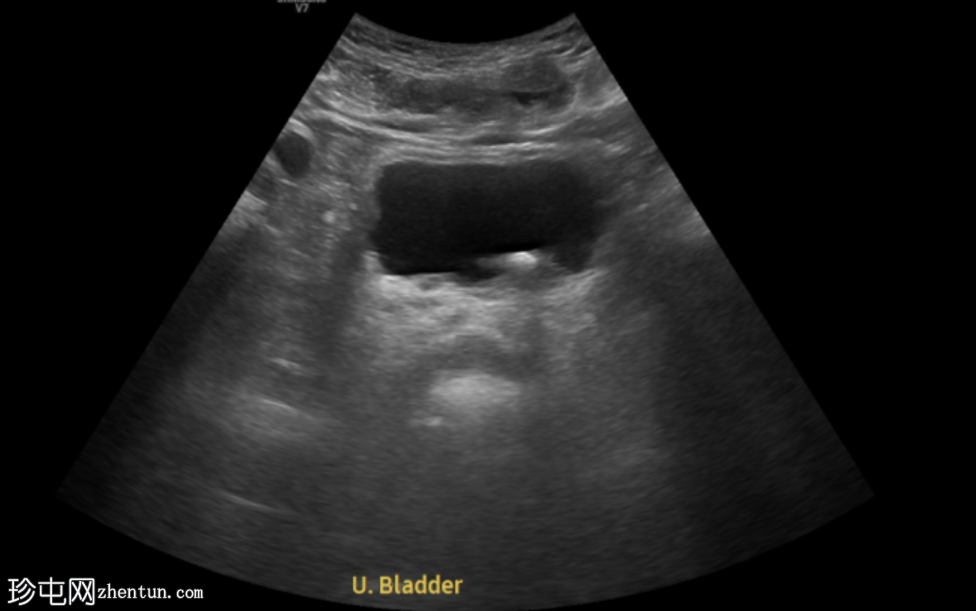

超声显示左侧轻度肾积水,由膀胱输尿管连接处一枚7毫米的远端输尿管结石阻塞所致,输尿管射流正常。

肾积水并非总是由输尿管结石引起。肾盂和肾盏扩张的程度与结石大小并不一定相关。

较小的结石有时可导致中度上游扩张,而较大的结石可能仅引起轻微的充盈感,这取决于患者的引流和水合状态。